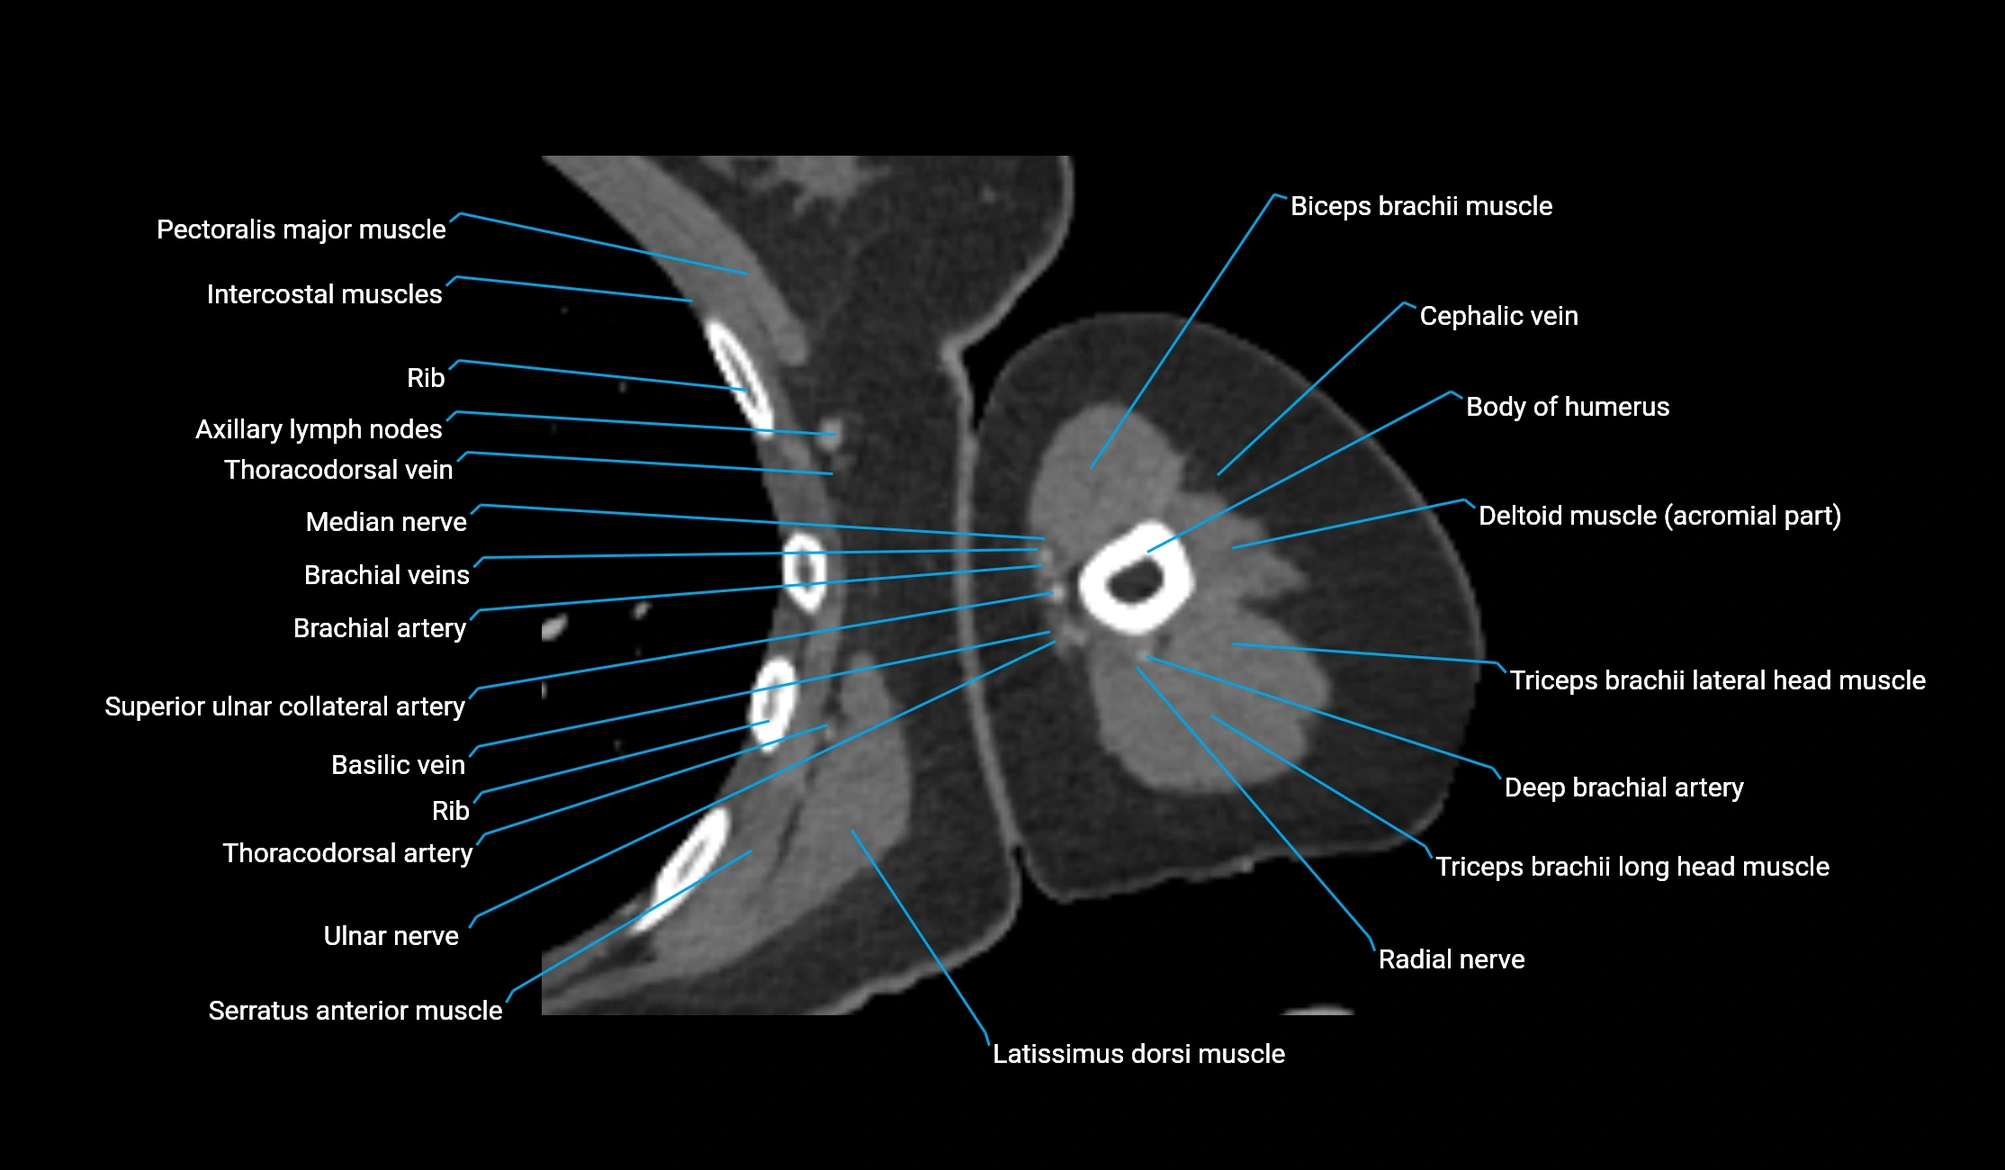

- Axillary lymph nodes

- Biceps brachii muscle

- Body of humerus

- Brachial artery

- Brachialis muscle

- Cephalic vein

- Clavicular part of deltoid muscle

- Deep brachial artery

- Long head of triceps brachii muscle

- Median nerve

- Pectoralis major muscle

- Radial nerve

- Superior ulnar collateral artery

- Thoracodorsal artery

- Ulnar nerve